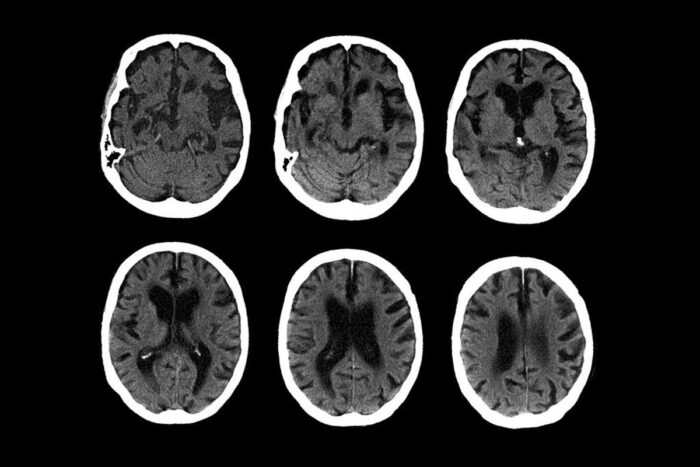

C.T. scans of the brain of a 74-year-old with Alzheimer’s diseaseZephyr/Science Source